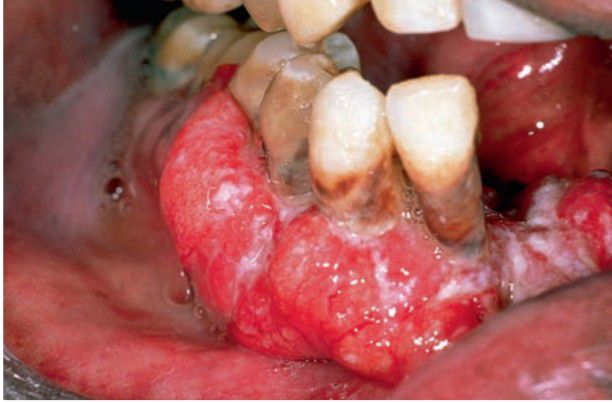

Squamous cell carcinoma of gingiva

Indurated, nonpainful ulcer with rolled margins; most commonly found on lateral tongue and floor of mouth; males affected twice as often as females. Gingiva is affected too.